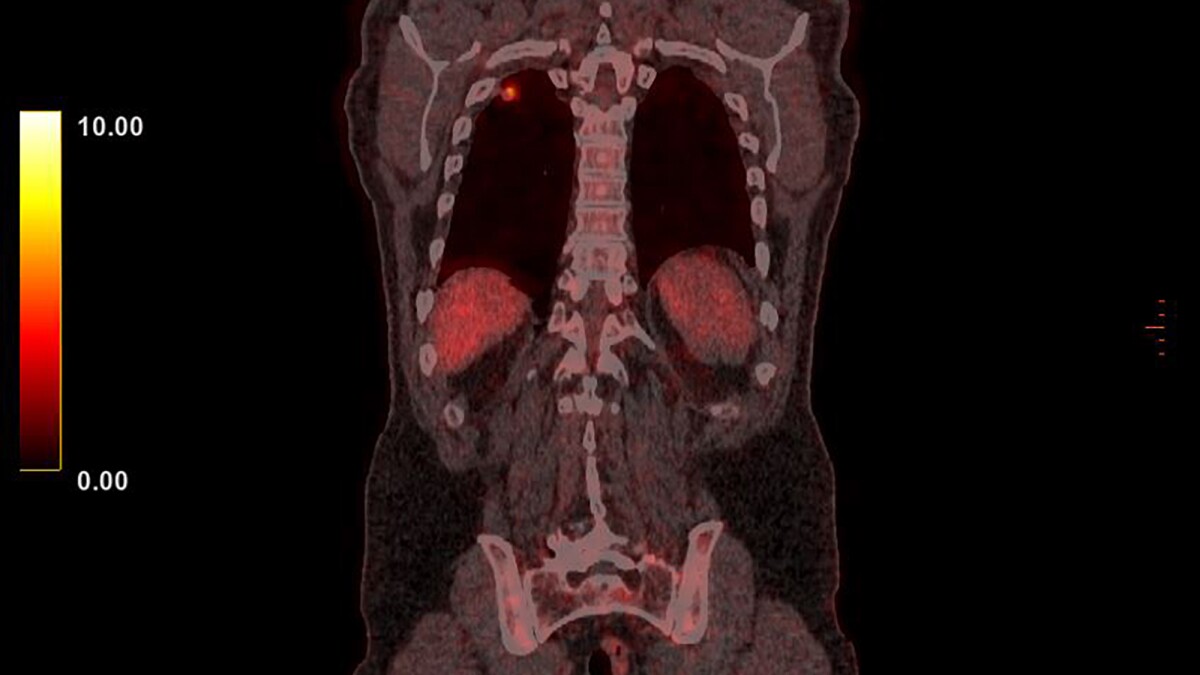

Researchers have published the results of a clinical trial evaluating the efficacy of an immunotherapy drug in treating a particularly aggressive form of lung cancer. Tarlatamab produced promising results, demonstrating antitumor activity and improving survival rates in patients for whom previous treatments hadn’t worked.